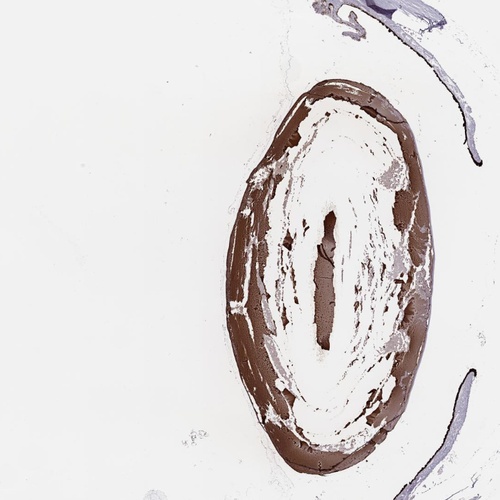

Immunohistochemical staining of human eye shows strong cytoplasmic positivity in the lens.